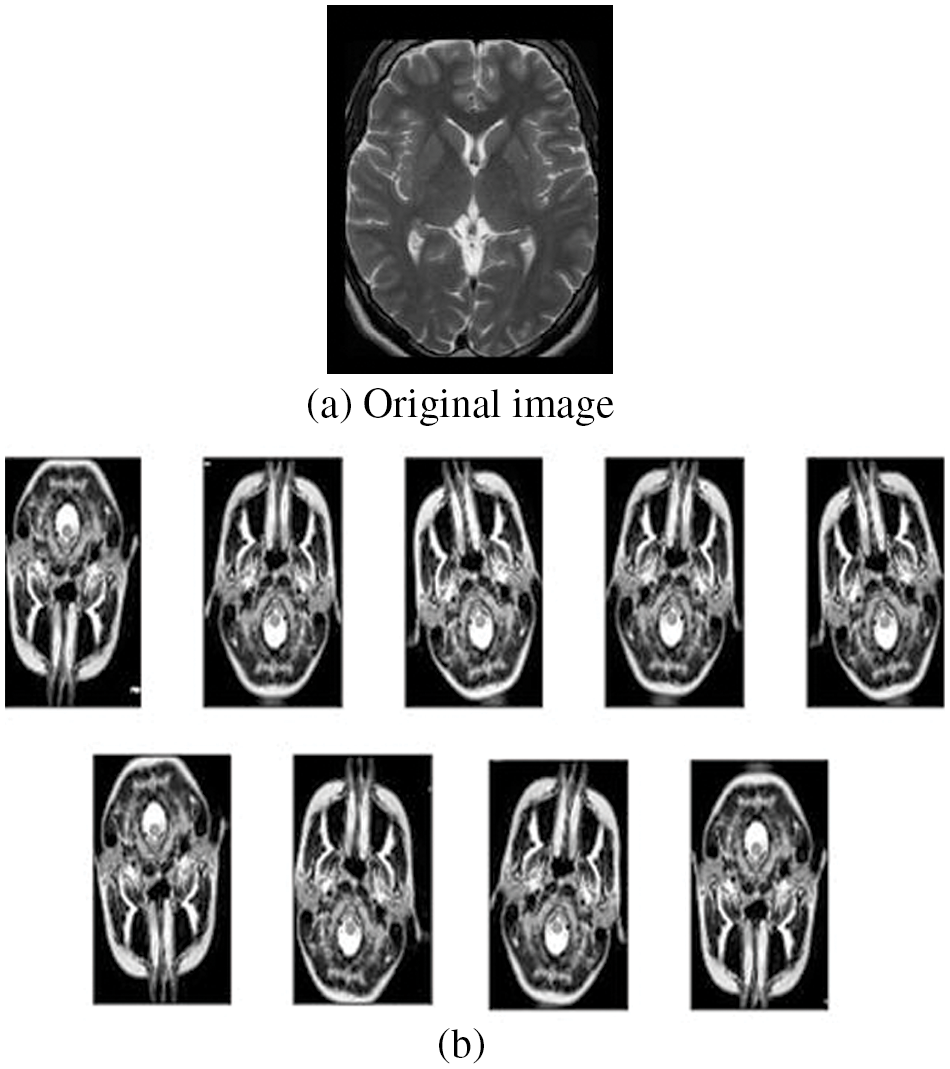

Further, the accuracy of the network can be enhanced through augmentation as the class meningioma have the smallest number of samples in the training set, and the most affected class in terms of misclassifications and Overfitting could be avoided by data augmentation. The following figure shows the original image (Fig. 6a) and the augmented images (Fig. 6b). The original image is increased in the ratio of 1:9 using features like rotation range (15 degrees), sheer transform, zoom in/out, flip, width shift, and height shift. Then the final augmented images are derived, as shown in the figure. The original database comprises 843 images which were then augmented to 8487 images, and these augmented images are used for training, validation, and testing for other processes.

Figure 6: Original and augmented images